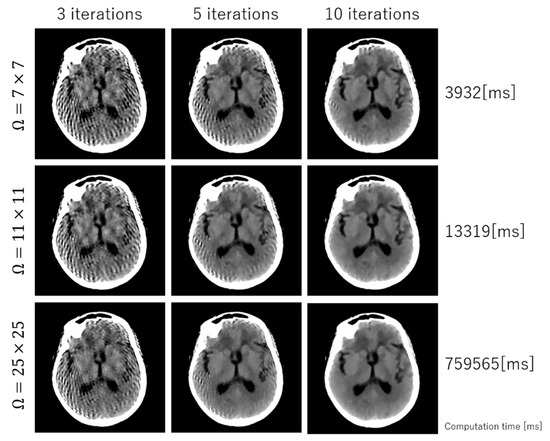

2. Methodology

2.3. Optimization

3. Experimental Results